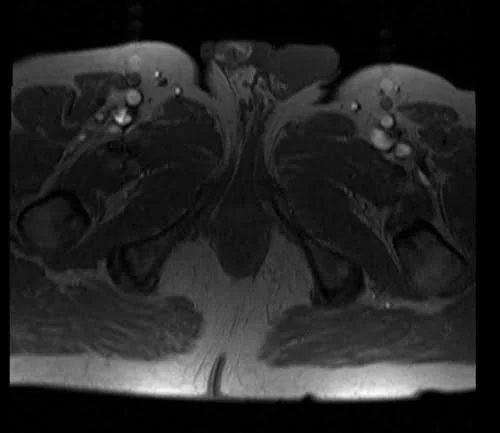

mri fistula localizer image 1 - MRI